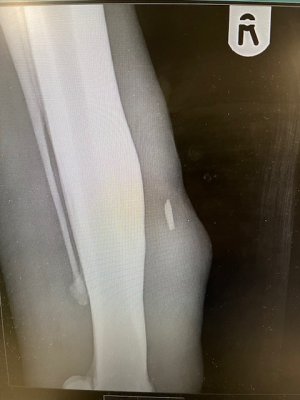

One of our ponies has been a bit off her game lately, so I got the vet here today. Her fetlock was painful when flexed, and on x ray they found a bone chip on her fetlock.

I plan to get it removed as it is obviously causing issues. Has anyone any experience of this please?